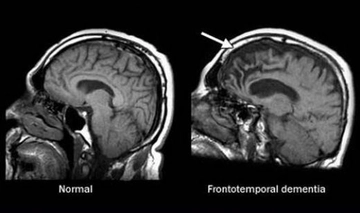

Belirtiler, hastalığın seyrine göre değişiklik gösterebilir ve bazı durumlarda hastalığın ilerlemesi ile birlikte yeni belirtiler ortaya çıkabilir. Nörolojik Hastalıkların TanısıNörolojik hastalıkların tanısı, detaylı bir tıbbi öykü ve fizik muayene ile başlar. Ayrıca, aşağıdaki tanı yöntemleri kullanılabilir:

Bu tanı yöntemleri, hastalığın türünü belirlemek ve uygun tedavi planını oluşturmak için kritik öneme sahiptir. Nörolojik Hastalıkların TedavisiNörolojik hastalıkların tedavisi, hastalığın türüne, belirtilerine ve bireyin genel sağlık durumuna bağlı olarak değişir. Tedavi yöntemleri genel olarak aşağıdaki başlıklar altında toplanabilir: